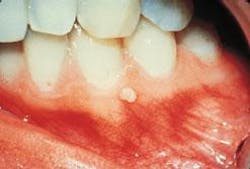

No significant extraoral findings were noted. Intraoral examination revealed an elevated, pale pink growth located on the attached gingiva in the area between teeth #21 and #22. The lesion appeared to be firm and measured approximately 2 millimeters in diameter. A slight papillary surface texture was noted.

The teeth adjacent to the lesion were pulp tested for vitality; both #21 and #22 tested vital. Further examination of the oral soft tissues revealed no other masses present.

Although the giant cell fibroma may be seen at any age, it typically is seen in individuals under the age of 30. The giant cell fibroma is asymptomatic and may appear smooth and nodular or papillary. The color is normal for the location, usually pale pink. The lesion may be pedunculated or sessile.

The giant cell fibroma usually measures less than one centimeter in diameter and is most often found on the gingival; the mandibular gingiva is affected more frequently than the maxillary gingiva. Other locations that may be involved include the tongue and palate.